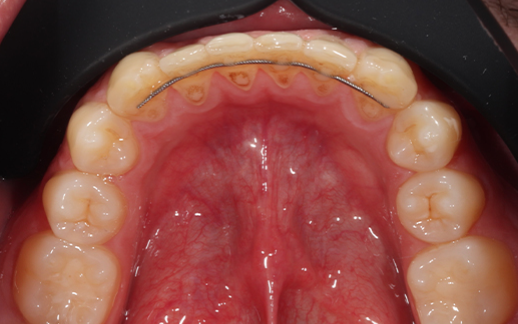

4 работы в портфолио

Установка брекетов

Установка брекетов в Москве

от 318 690 ₽

до 345 690 ₽